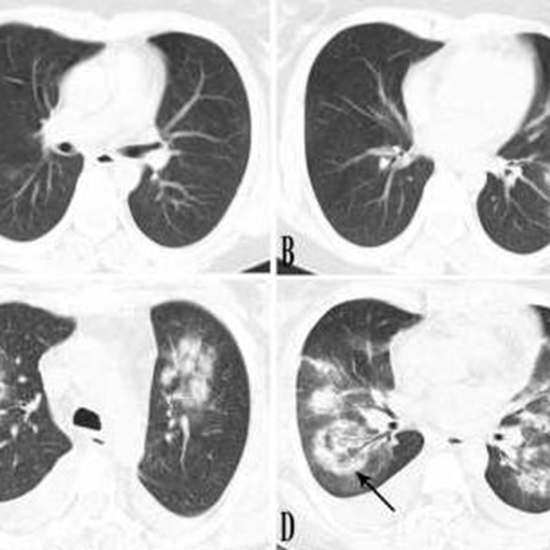

Is Target Sign (Bull’s Eye Appearance) associated with adverse outcomes in COVID-19 patients? A Case Series and Literature Review

In COVID-19 pneumonia, chest CT scan plays a crucial role in diagnosing and closely monitoring lung parenchyma. The main reportedly chest CT features of novel coronavirus pneumonia (NCP) have been fully discussed in the literature, but there is still a paucity of reports on uncommon CT manifestations.

Herewith, we have reported ten rRT-PCR confirmed COVID-19 patients with CT target signs (bull’s eye appearance); additionally, we have reviewed previously reported cases. Reviewing the literature, we found eight COVID-19 patients with target sign in the literature. 18 patients were included with a median age of 43. 11 (61%) patients were males. In 87% of patients, the lesions developed within the second-week post symptom onset. These patients mostly experienced an extended hospital stay (median = 10 days), with 53.8% of cases being admitted in ICU. The in-hospital mortality rate was 23%.

Our findings indicate that lesions with a bull’s eye appearance are not significantly associated with higher mortality in hospitalized COVID-19 patients